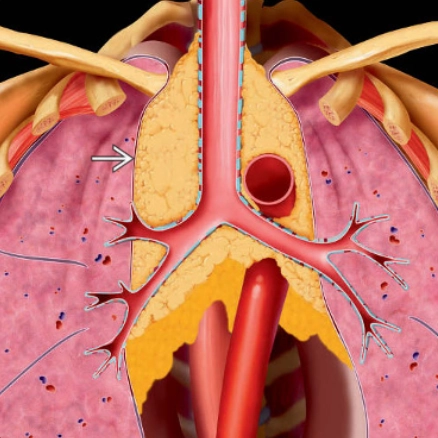

U mỡ tuyến ức (Thymolipoma)